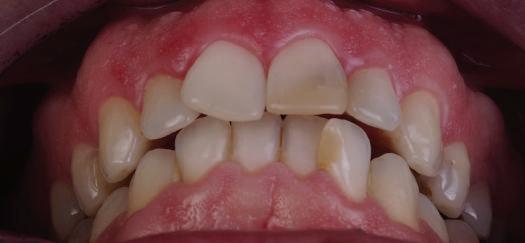

20 Dental Tribune Bulgarian Edition / октомври 2022 г. П ациентите със завършен растеж и скелетни проблеми обикновено представляват предизвикателство за ортодонт ската практика. Необходимостта от изваждане на зъби в комбинация с особеностите на възрастовата ортодонтия изисква особено внима ние. Фокусът върху критично важното значение на позицията на долните резци във връзка с дългосроч ната стабилност и постигането на оптимални оклузални взаимоотношения при затварянето на екстракционните пространства лесно може да излезе извън контрол. Когато към тези чисто кли нични проблеми се добави и стресът от натоваре ната практика, предизвикателството става още по-голямо. Всички тези фактори налагат използ ването на доказан подход с ясни и последовател ни стъпки, в което се разкрива силата на дисциплината „Алекзандър“ – предвидим протокол през целия процес на елиминиране на ротациите, ниве лиране на дъгите, затваряне на екстракционните пространства и финализиране на случая. Именно такъв е и случаят, който презентираме –екстракционен, скелетен клас 3 при възрастен па циент, лекуван по системата „Алекзандър“. ПРЕДВИДИМИ РЕЗУЛТАТИ ПРИ ПАЦИЕНТИ СЪС ЗАВЪРШЕН РАСТЕЖ И СКЕЛЕТЕН КЛАС 3, ИЗПОЛЗВАЙКИ ЕКСТРАКЦИОННО ЛЕЧЕНИЕ ПО ДИСЦИПЛИНАТА „АЛЕКЗАНДЪР“ Д-р Радой Димитров, България Преди започване на лечение клиничен случай | ортодонтия Фиг. 1а–1e Преди започване на лечение. Пациентът пристига в практиката с основното оплакване от невъзмож ност за нормално дъвчене. Снета е цялата необходима диагностична ин формация. Фиг. 1f–1h Снимки в профил и анфас. Фиг. 1i–1k Панорамна снимка, телерентгенография и анализ на телерент генография. Фиг. 1а Фиг. 1d Фиг. 1f Фиг. 1g Фиг. 1h Фиг. 1e Фиг. 1b Фиг. 1c Фиг. 1i Фиг. 1j Фиг. 1k

closed.

21Dental Tribune Bulgarian Edition / октомври 2022 г. ДИАГНОСТИЧНИ РЕЗУЛТАТИ: 1. Възраст на пациента: 21 години 2. Скелетен клас III (ANB 0) 3. Зъбен клас 3 4. Ръбцова захапка във фронта, кръстосана в дисталните участъци 5. Тясна горна челюст 6. Overjet – 0 мм, Overbite – 0 мм 7. Несъответствие на горната с долната средна линия 8. Единични контакти в ЦО 9. Хиподивергентен тип на растеж SN/MP – 33.5 10. Неравен гингивален контур 11. Неравна линия на усмивката 12. Тенденция за рецесии в долен фронт ПРЕПОРЪЧИТЕЛНО ЛЕЧЕНИЕ: Пълно ортодонтско лечение с метални брекети „Алекзандър“ Корекция на клас 3 захапката в областта на кучешките зъби с екстракция на първите пре молари в долна челюст Корекция на кръстосаната захапка в дистални участъци Коригиране на ръбцовата захапка във фронта Подобряване на ОJ и OB на пациента Стрипинг в долен фронт Подреждане на зъбите в горната и долната челюст Професионално хигиенизиране и профилактични дентални прегледи са препоръчителни на всеки 6 месеца. 1-ви месец След 1 месец са залепени брекети в горната челюст – поставена е еластична дъга. 016 NiTi. В долната челюст са елиминирани ротациите, поставена е стоманена дъга. 016SS, закалена с ток, и еластична верижка за затваряне на пространствата. 3-ти месец В долната челюст е поставена трета дъга – 17 x 25 NiTi с къси лигатури и верижка

В горната челюст се затварят пространствата с дъга .016SS и верижка. 5-и месец На 5-ия месец след залепяне на брекетите в долната челюст е поставена стоманена дъга 16 x 22 SS с четвъртито сечение, омега луп и тай бек. В горната челюст е поставена дъга 17 x 25 NiTi. Поради липсата на стабилни оклузални контакти са поставени лингвални верижки в областта на моларите, за да се предотврати нежелана ротация на 7-ите зъби. 6-и месец На 6-ия месец от началото на лечението са екстрахирани долните първи премолари, поставена е дъга 16 x 22 SS със затваряща чупка teardrop. Чупката се активира всеки месец по 1 мм с чинч-бек. клиничен случай | ортодонтия СТЪПКИ НА ЛЕЧЕНИЕТО Начало на лечението Лечението започва с поставяне на апарат за бърза експанзия в горната челюст. През първия месец от лечението са направени 24 оборота на апарата за експанзия. Залепени са брекети в долната челюст, поставена е дъга 17x25 CuNiTi, като са предпи сани клас 3 ластици (1/4”,4 1/2 oz) по време на сън, за да се осигури контрол върху торка на долните резци. Фиг. 2а Фиг. 3a Фиг. 4a Фиг. 3b Фиг. 4b Фиг. 3c Фиг. 4c Фиг. 3d Фиг. 4d Фиг. 3e Фиг. 4e Фиг. 5a Фиг. 5b Фиг. 5c Фиг. 5d Фиг. 5e Фиг. 6a Фиг. 6b Фиг. 6c Фиг. 6d Фиг. 6e Фиг. 7a Фиг. 7b Фиг. 7c Фиг. 7d Фиг. 7e Фиг. 2b Фиг. 2c Фиг. 2d

Dental Tribune Bulgarian Edition / октомври 2022 г.22 клиничен случай | ортодонтия 14-и месец В горната и долната челюст са поставени последни стоманени дъга с омега луп и тай бек – 17 x 25 SS с четвъртито сечение. Назначени е ластик за средната линия в комбинация с клас 3 ластик (1/4”, 6 1/2 oz). Контролни рентгенографии 13-и месец Екстракционните пространства са затворени. Направена е контролна панорамна снимка за оценка позицията на корените. Взето е решение за презалепване на брекетите на 12, 22 и пръстените на 36 и 46. 21-ви месец Средната линия в горната и долната челюст съвпадат. Ластиците са спрени. Свалени са пръстените и брекетите в горната и долната челюст, зигзаг ластици не са използвани поради благоприятните оклузални взаимоотношения. Фиг. 11j Ортопантомография в края на лечението. Фиг. 11k Телерентгенография след края на лечението. Фиг. 11l Анализ на телерентгенографията след лечението. Фиг. 11m Последователност на дъгите в горната и долната челюст Фиг. 11n Суперимпозиция на PreOp и PostOp ортопантомографии. 10-и месец Затварянето на пространствата е предвидимо и контролирано, без да се отварят пространства в зъбната дъга. Фиг. 8a Фиг. 8b Фиг. 8c Фиг. 8d Фиг. 8e Фиг. 10a Фиг. 10b Фиг. 10c Фиг. 10d Фиг. 10e Фиг. 9a Фиг. 9b Фиг. 9c Фиг. 9d Фиг. 9e Фиг. 9f Фиг. 11a Фиг. 11f Фиг. 11j Фиг. 11l Фиг. 11m Фиг. 11n Фиг. 11k Фиг. 11g Фиг. 11h Фиг. 11i Фиг. 11b Фиг. 11c Фиг. 11d Фиг. 11e

Dental Tribune Bulgarian Edition / октомври 2022 г. 23клиничен случай | ортодонтия реклама Лечението е продължило 21 месеца. Проведено е домашно избелване с индивидуални шини. За автора: Д-р Радой Димитров завършва с отличие Факултета по дентална медицина към МУ–София през 2015 г. В продължение на 5 години работи в няколко водещи практики в София, като през 2019 г. заедно със своята съпру га д-р Траяна Димитрова основават собствена практика в гр. Гоце Делчев –Dimitrovi Dental Care. Посещава редица курсове за повишаване на квалификаци ята, но най-сериозен тласък в развитието на ортодонтската си практика получава след завършването на комплексната ортодонтска програма, воде на от д-р Иван Горялов, базирана на дисциплината „Алекзандър“ – система с повече от 50 години опит в целия свят. Д-р Димитров е член на Българския изследователски клуб „Алекзандър“. Взе ма участие като гост-лектор в симпозиума с международно участие The Power of the Alexander Discipline, който се проведе на 14–15.05.2022 г. С д-р Ди митров можете да свържете на тел. +359885 252 025. Заключение Представеният случай е ярък пример за възможностите и красо тата на дисциплината „Алекзандър“ – приложен е утвърден под ход с ясни правила и са постигнати очакваните цели. Резулта тът ще бъде дългосрочно стабилен, тъй като са спазени всички правила, които се отнасят към максимално комфортната пози ция на зъбите в края на лечението. Постигнати са красива усмив ка и стабилна оклузия. ПОСТИГНАТИ РЕЗУЛТАТИ ОТ ЛЕЧЕНИЕТО 1. Коригирана ръбцова захапка 2. Коригирана клас 3 захапка в областта на ку чешките зъби 3. Коригирана кръстосана захапка в дисталните участъци 4. Коригиран овърджет и овърбайт 5. Разширена е горната зъбна дъга 6. Подредени зъби в горната и долната челюст 7. Постигната е стабилна захапка с множество контакти в ЦО 8. Драматично е подобрена дъвкателната функ ция 9. Подобрена е линията на усмивката ДРУГИ ПРОВЕДЕНИ ДЕНТАЛНИ ПРОЦЕДУРИ 1. Домашно избелване на зъбите 2. Екстракция на мъдреците Фиг. 12a Фиг. 12b Фиг. 12c Фиг. 12eФиг. 12d Фиг. 12f Фиг. 12g Информация за дати, цени и отстъпки www.bracescourses.com 0889 22 55 01 Практически курсове лектор д-р Иван Горялов Дисциплината „Алекзандър“ ПЪТЯТ КЪМ СУПЕРУСМИВКИТЕ 100% връщане на цялата сума, ако не сте удовлетворени след преминаване на Ниво 1 Директно и индиректно залепяне на брекети Анализ, диагноза и план на лечение Лечение на клас 2 дълбока захапка Екстракционно лечение Лечение на клас 3 отворена захапка НИВО 5НИВО 1 НИВО 2 НИВО 3 НИВО 4